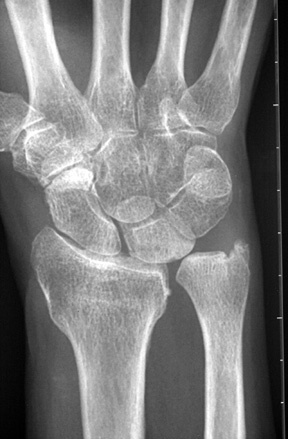

Diagnosis? Etiology?

Keinbochs

What conditions are associated with the pathological finding of this XR? What would you expect to find on physical exam?

Ulnar Positive Variance

What conditions are associated with the pathological finding of this XR?

Ulnar Negative Variance